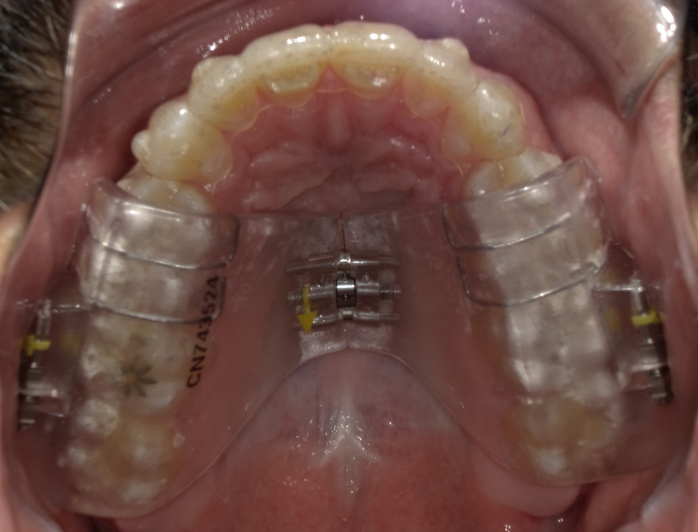

Fig 10. The appliance worn during treatment, anterior view (Fig 8), right side view (Fig 9), left side view (Fig 10), and upper arch view (Fig 11).

Figure 10

Intraoral scans were taken to document the patient's entire palate and bite registration. Scans were sent to the clinical team for the fabrication of a clear aligner/sleep appliance for the patient to wear; the chosen appliance fits over clear aligners, regardless of the tray number the patient may need (Figure 7 through Figure 11).

After the appliance was delivered, additional photographs were taken with the camera to ensure that the appliance was delivered as intended, to document the case, and to show the patient the ideal fit of the appliance in his mouth as instructions were reviewed with him.